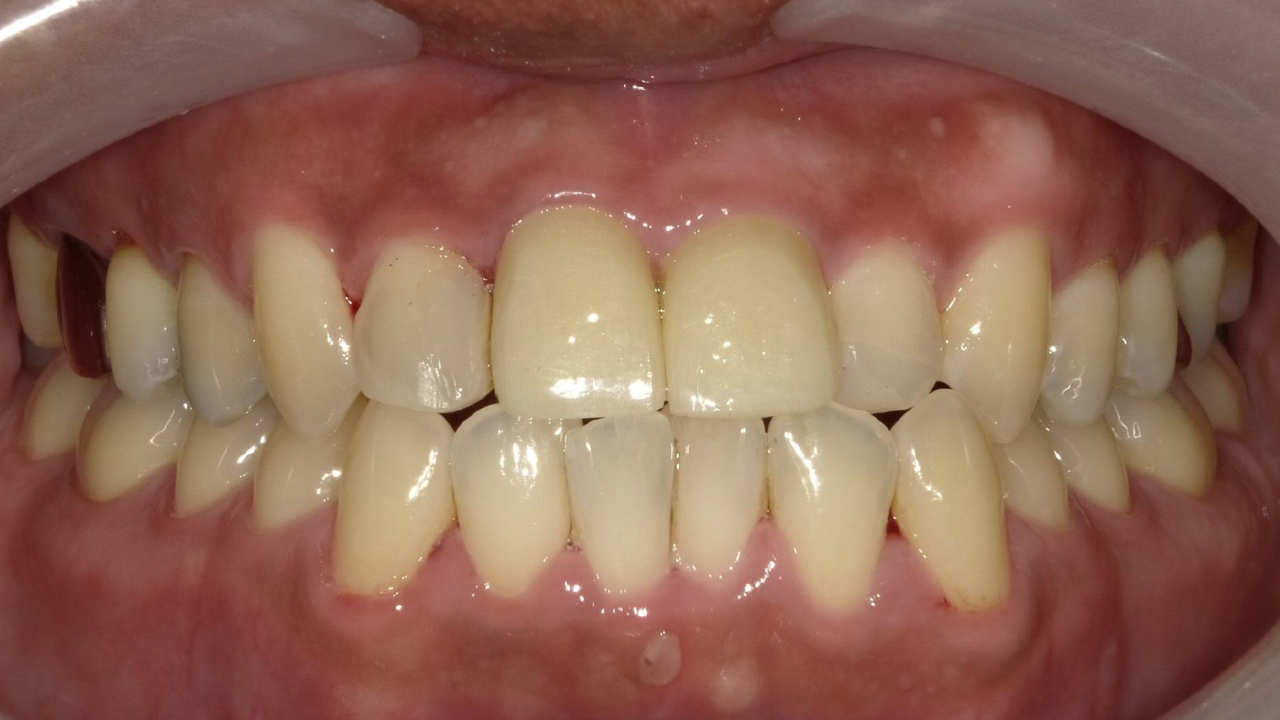

T・K様 男性 30代

Before

After

キックボードで転倒し前歯を受傷されました。上の前歯は2本とも歯冠が割れていて歯の神経が見えている状態でした。抜歯はせず、歯を出来る限り残した治療を予定しました。神経の治療後、審美的にジルコニアクラウンを希望されました。治療後は痛みもなく、見た目も綺麗で抜歯もせず治療ができたと大変満足されていました。

治療期間・回数:2か月、6回

治療の価格:ジルコニアクラウン ¥137,500(1歯)

治療のリスクや副作用:保険適応外。特にジルコニアは硬度が高いため、素材の厚みを確保するために歯を多く削ることがある点がデメリットです。